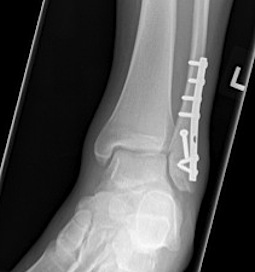

Many fractures can be treated without surgery, if the fractures are in place anatomically and can be maintained in this position with a cast. When there is significant displacement, or indications that there is significant ligament injury, surgery is recommended.

The main risk of the surgery is infection. This risk is low, about 1/100. Reducing swelling after surgery is critical, so keeping it up in the air when sitting or lying is very important. There can be some numbness around the incision, and there is a small risk of deep vein thrombosis. Usually there must be a period of non weight bearing for six weeks while the injury heals; however, early range of motion is useful to prevent or minimize stiffness. It can take 6 – 12 months to fully recover from these injuries.